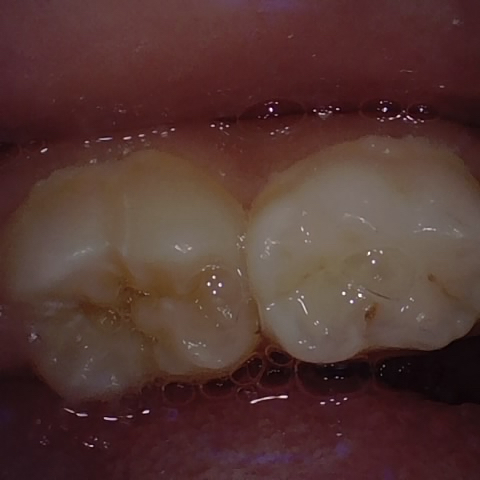

NHD39177

Annotated as "Good"

Original Image Rendering Image